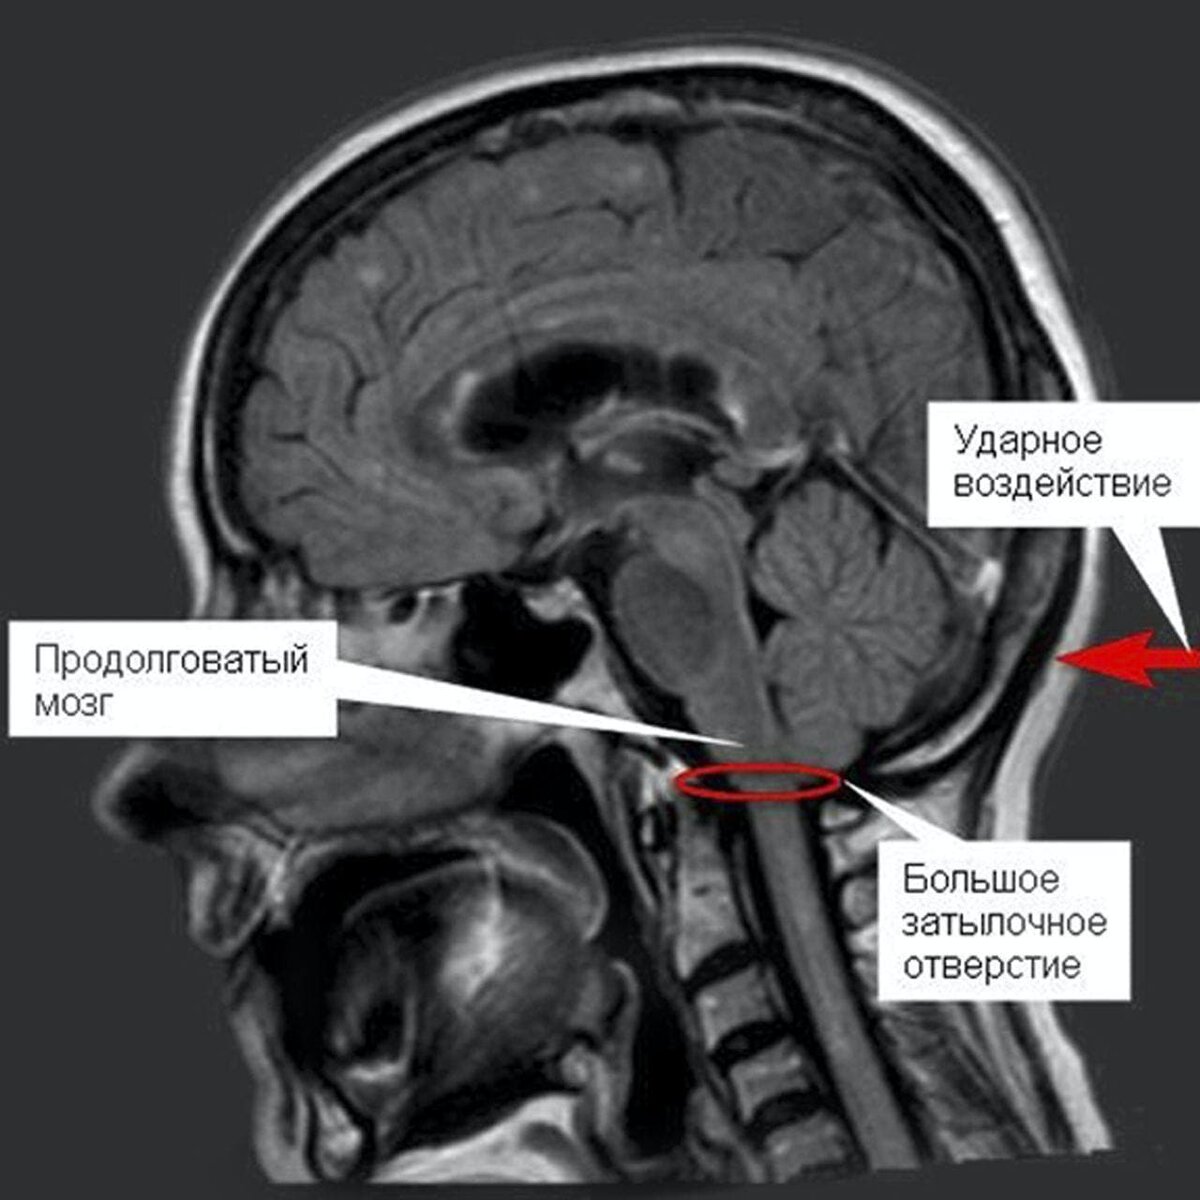

Почему не стоит бить "подзатыльники"?

Все дело в затылочном отверстии черепа, в котором находится продолговатый мозг — непосредственное продолжение спинного мозга. В его ядрах находятся жизненно важные центры. Например: регуляторы кровообращения (регуляция тонуса сосудов), дыхания, моргания. Поэтому, даже самый легкий удар по затылочной части может привести к нарушению зрения, обмороку, остановке дыхания или летальному исходу. Подписывайтесь на канал, на нём много интересных статей, в которых я рассказываю об особенностях нашего организма! И не забывайте поставить палец вверх!